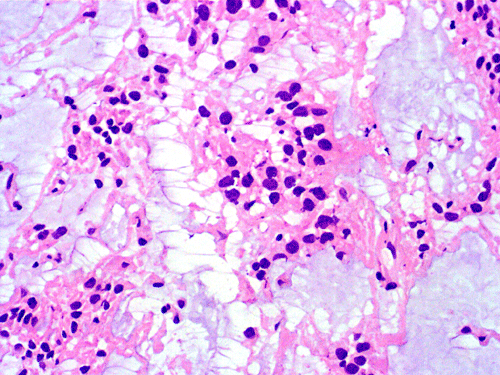

On cytologic preparations, there are clumps of tissue that do not smear out well (Panel A). On higher magnification, these tissue clusters are composed of large blobs of bluish, acellular, mucoid material admixed with cells with relatively uniform, bland nuclei and small amount of cytoplasm (Panel B). In the less tightly packed areas, the long cytoplasmic processes of the cells can be well appreciated (Panel C). These long processes are highly suggestive of a glial neoplasm. On frozen sections, the lesion is composed of multiple blobs of bluish, mucoid material surrounded by tumor cells (Panel D and E). Features of the paraffin sections are not that much different from that of the frozen sections (Panel F G H).